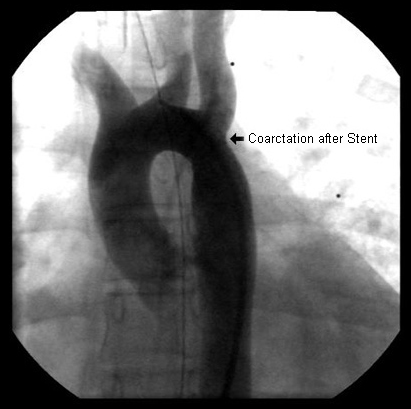

After stent placement, the narrowed area is markedly improved

From the personal collection of Jeffrey Gossett, MD, Children's Memorial Hospital, Northwestern University, Chicago; used with permission